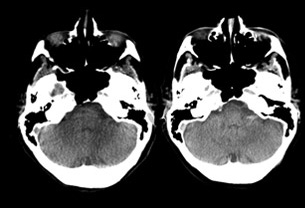

Avoiding motion artifacts in restless patients, enabling enhanced depiction of bleeds and avoiding cone-beam artifacts -especially in the posterior fossa- are important elements of the ongoing research.8

Hemorrhage detection. Comparison between optimized XperCT and Multi Detector CT.9